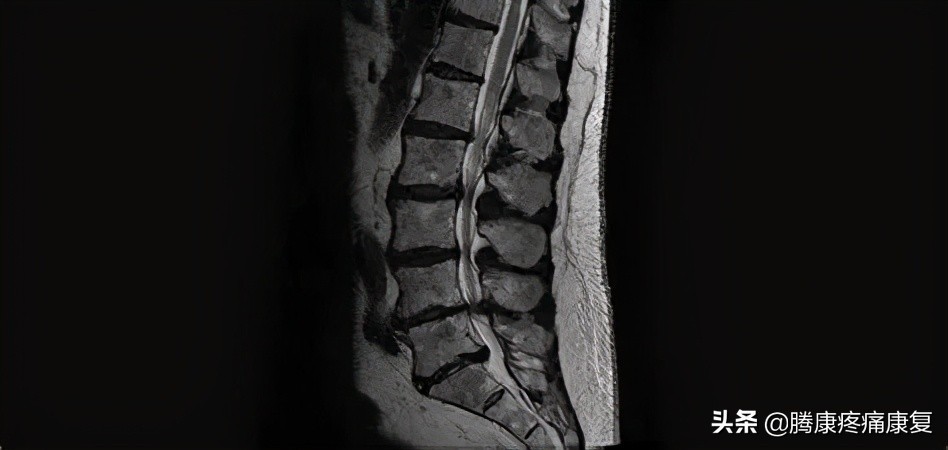

- 磁共振成像对椎间盘异常,包括纤维环撕裂和椎间盘突出非常敏感。